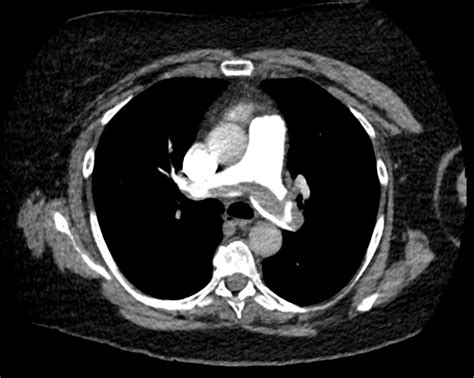

The two-tier model is frequently used in emergency departments to streamline decision-making. If a patient is classified as "PE unlikely," a D-dimer test is often the next step to effectively rule out the condition. If the patient is classified as "PE likely," clinicians often bypass D-dimer testing and proceed directly to definitive imaging, such as a computed tomography pulmonary angiography (CTPA).

The Role of Diagnostic Imaging and D-Dimer

The integration of the Pulmonary Embolism Wells Score with laboratory diagnostics is what makes the management of suspected PE efficient. D-dimer is a fibrin degradation product; its levels are typically elevated in the presence of a thrombus. However, D-dimer is highly sensitive but not very specific. This means a negative D-dimer is excellent for ruling *out* a PE, but a positive result does not necessarily confirm one.

When the Wells Score indicates a low or moderate probability of PE, a negative D-dimer result is often enough to discharge the patient safely. This workflow protects patients from unnecessary imaging while maintaining high diagnostic accuracy. It is this synergy between clinical assessment and laboratory evidence that defines modern, high-quality emergency medicine.